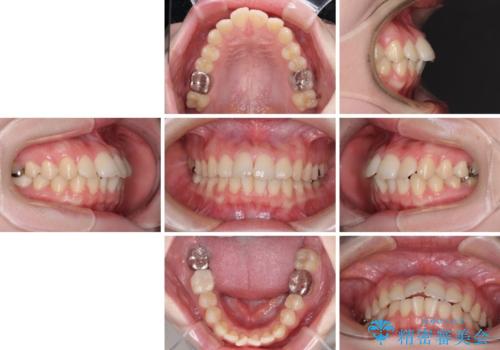

- 上下歯列全体のデコボコを気にして来院された患者様です。

主に下顎歯列全体の後方移動とIPR(歯と歯の間を削る)によってデコボコが解消するように設計し、インビザラインにより治療を行うこととしました。

1年半程度で終了するのではないかと予想しましたが、途中1年以上の来院がなく、トータルで3年の時間がかかってしまいました。

前歯のデコボコはより改善することが望ましい状態でしたが、患者様の希望により終了することとなりました。